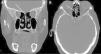

ResultadosDos pacientes presentaron meningitis como primer signo. En todos los pacientes se diagnosticó la rinolicuorrea mediante el análisis bioquímico del moco. La TAC y la RNM dieron indicios claros para la localización del punto de fuga. El defecto basicraneal fue siempre menor de 1cm. La fluoresceína permitió visualizar la zona fistulosa sin necesidad de otros instrumentos y no tuvo efectos secundarios. Un paciente sufrió un absceso frontal en el postoperatorio que evolucionó favorablemente. Todas las fístulas se cerraron y solo hubo una recidiva a los 10años que empezó como una meningitis neumocócica.

ResultsTwo patients had meningitis as the first sign. All patients were diagnosed by biochemical analysis of rhinorrhoea. CT and MRI gave clear evidence of the leakage location. The skull base defect was always less than 1cm. Fluorescein allowed clear visualisation of the fistulous area without other instruments and produced no side effects. One patient had a postoperative frontal abscess, which evolved favourably. All fistulas were closed and there was only one recurrence at 10years, which debuted as pneumococcal meningitis.